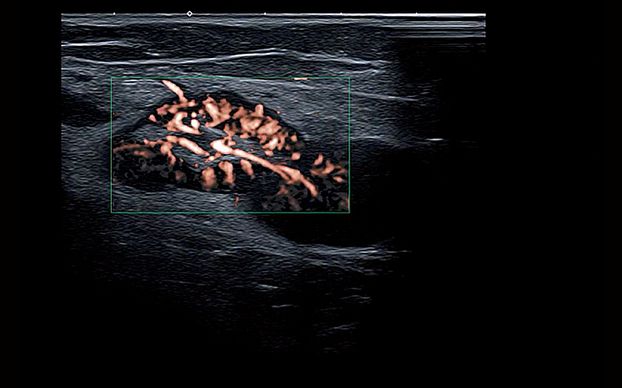

- Технология SMI для визуализации микроциркуляторного русла и отображения низкоскоростного кровотока в микрососудах

- SMI – Superb Micro-vascular Imaging (технология визуализации микроциркуляторного русла позволяет отобразить низкоскоростной кровоток в микрососудах)